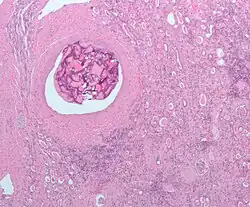

Micrograph of embolic material in the artery of a kidney. The kidney was surgically removed because of cancer. H&E stain.